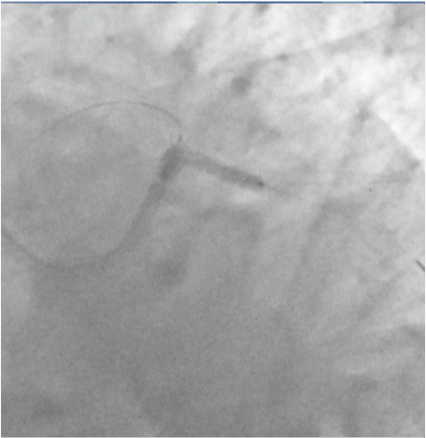

A check shot done at this stage of the procedure demonstrated fully expanded LM-LAD and LCX stents with brisk TIMI 3 flow into both arteries, but large fragments of thrombi appeared in the LAD artery (Figure 10), (Video 3) The patient complained of chest discomfort and this was accompanied with slight lowering of heart rate and drop in blood pressure. An intra-coronary (IC) bolus injection of tirofiban (20mcg/Kg) was immediately administered and this rapidly completely lysed the thrombi in the LAD artery (Figures 11 & 12), (Video 4). The patient was shifted to the CCU on intra-venous tirofiban infusion for the next 18 hours. His further stay in hospital was unremarkable, and he was discharged on the third day in stable condition on aspirin, prasugrel, atorvastatin, ramipril and metoprolol.

Figure 10 Check shot done after kissing balloon shows large burden of thrombi in LAD artery and no re-flow in distal artery, necessitating intracoronary high doses tirofiban administration ( 25mcg/Kg).

Figure 11 Fully expanded ( angiographically) stents in LM-LAD and LCX arteries, with TIMI 3 flow and no dissection.

Figure 12 Fully expanded LM-LAD and LCX stents with brisk TIMI 3 ante grade flow in both arteries.